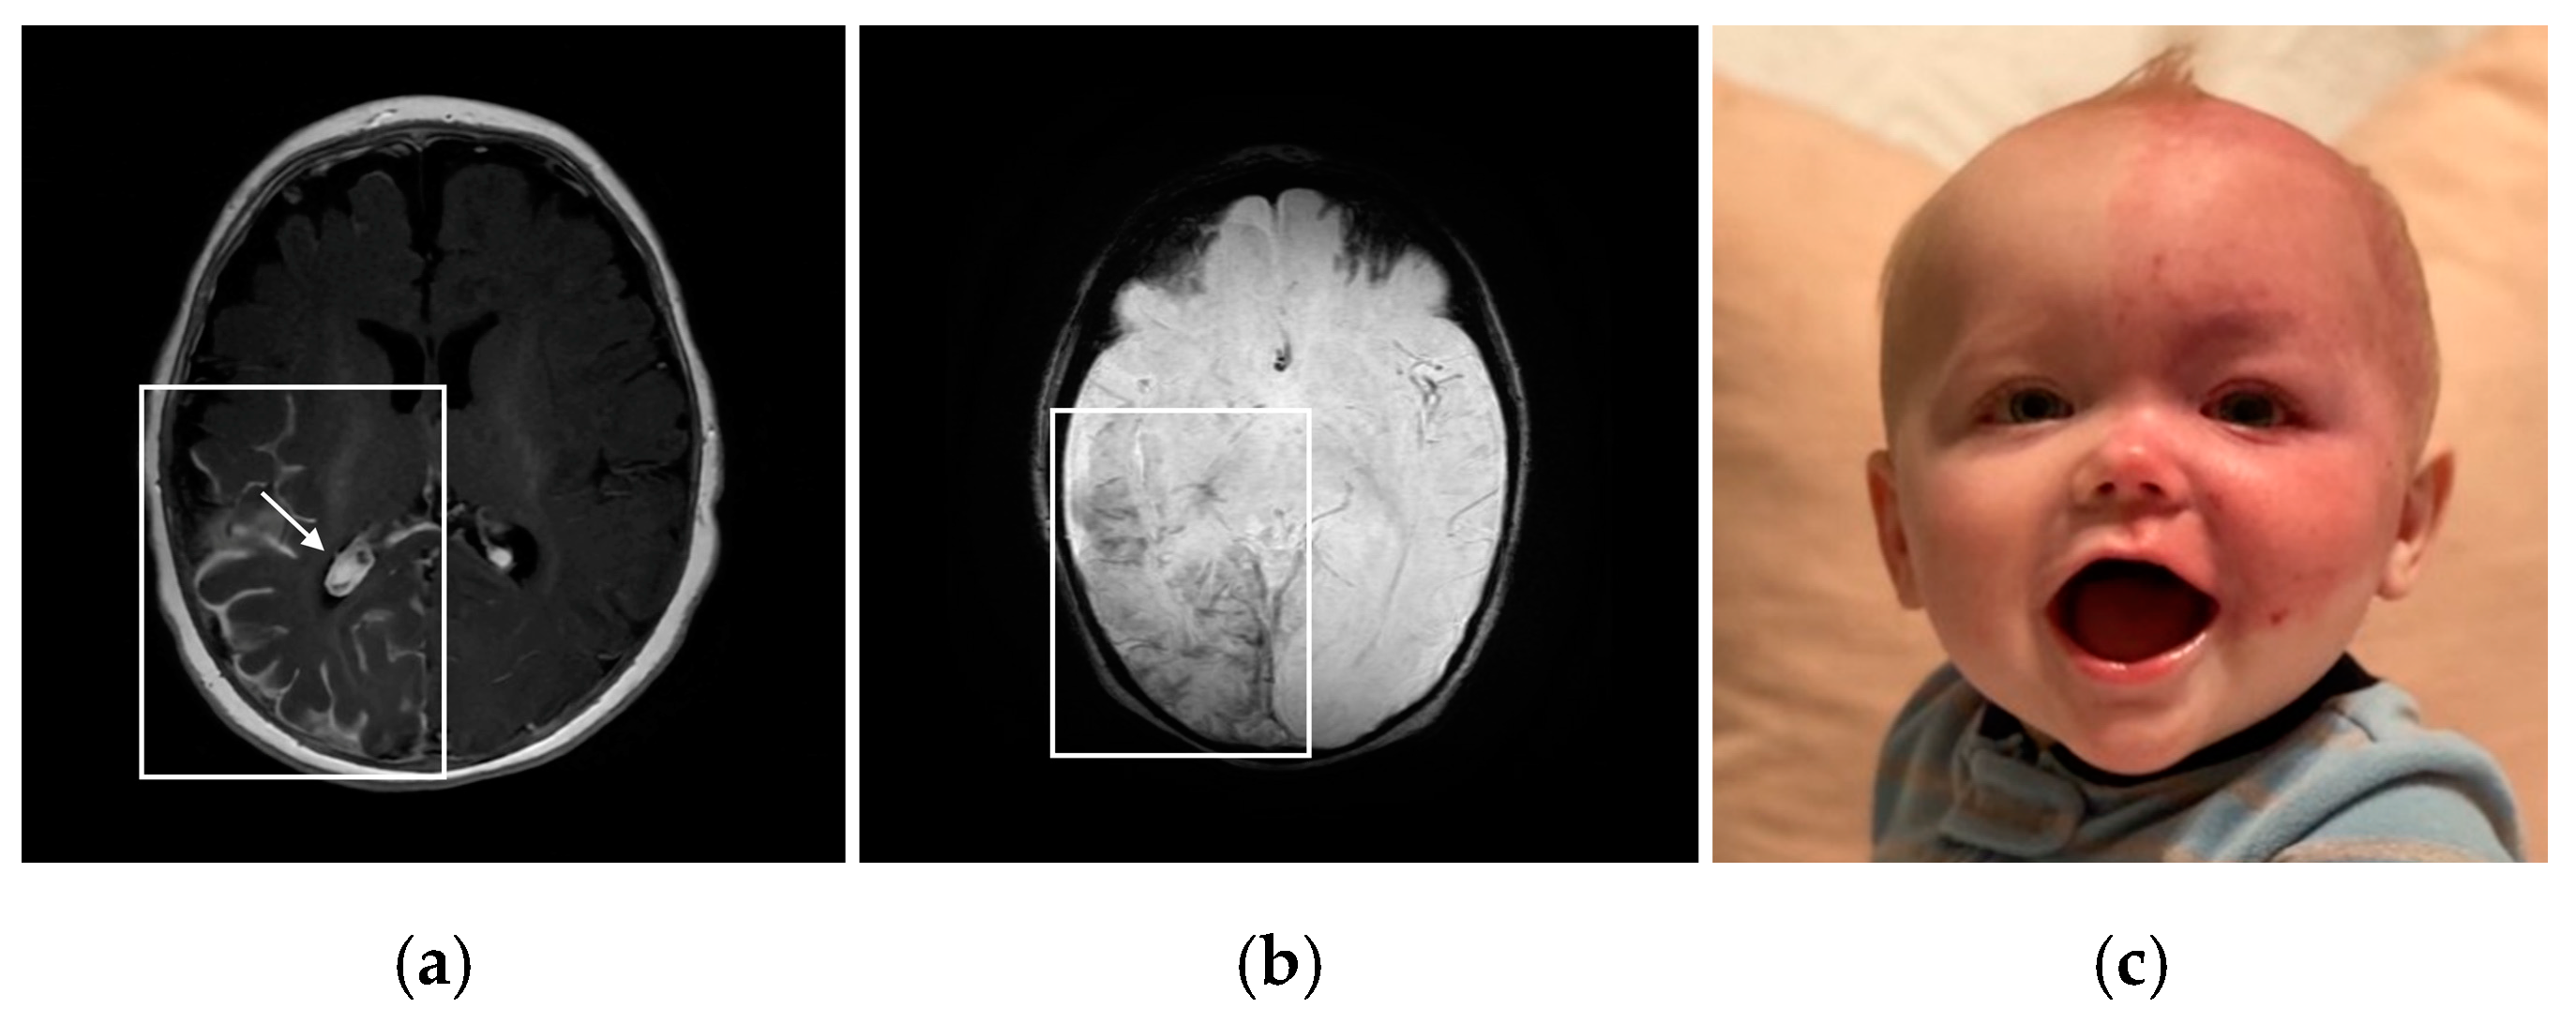

2.2. Brain Involvement